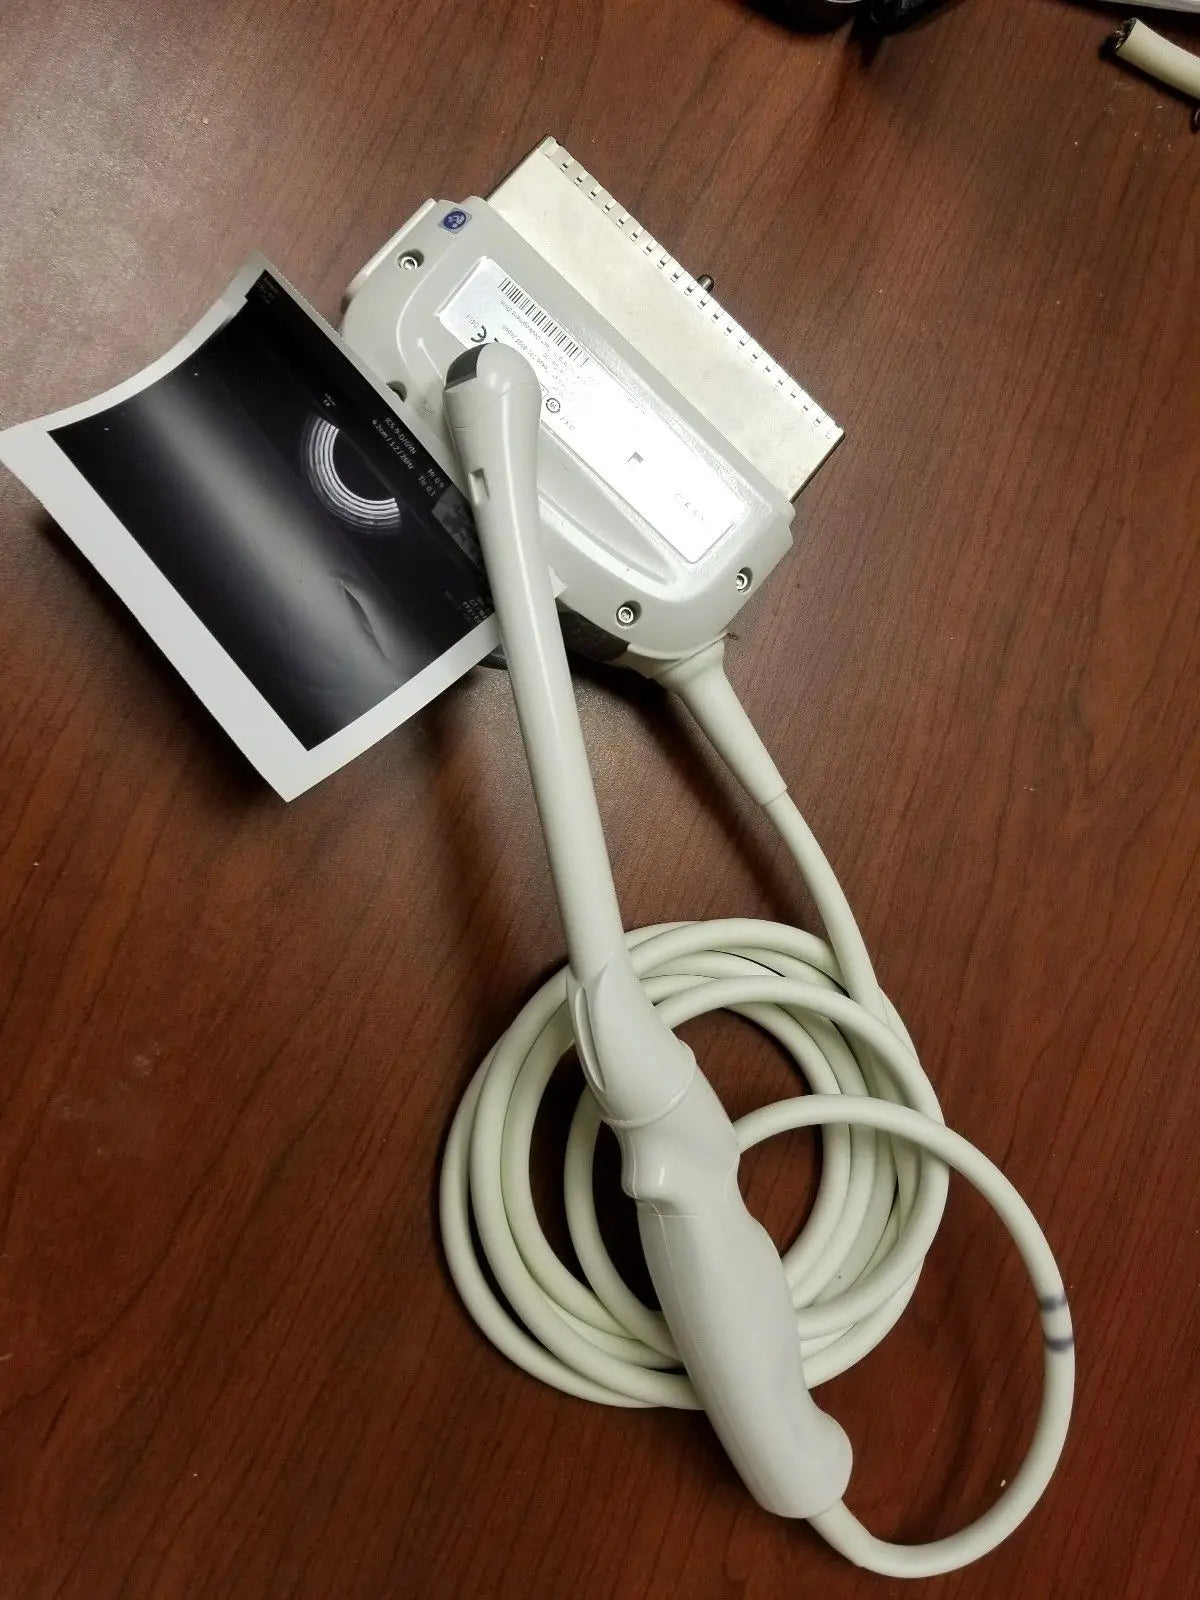

2017 GE IC9 -RS probe for GE Ultrasound

Sale price$ 8,395.14